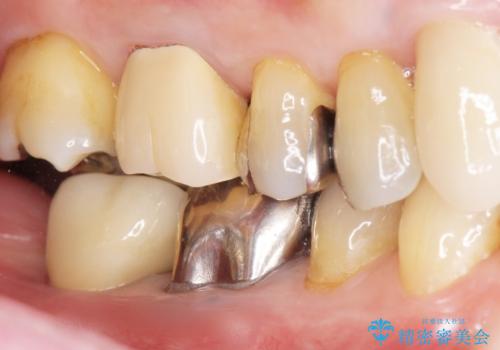

[ 重度歯周病 ] インプラント・義歯による咬合再構築

![[ 重度歯周病 ] インプラント・義歯による咬合再構築の症例 治療後](https://seimitsushinbi.jp/wp/wp-content/uploads/2021/07/4c6838854beaf5801dbc7fde26492d6c-500x350.jpg?v=1626759531)